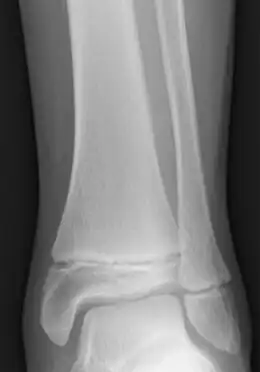

- ↑ Crowder et Austin, « Age ranges of epiphyseal fusion in the distal tibia and fibula of contemporary males and females », Journal of Forensic Sciences, vol. 50, no 5, , p. 1001–7 (PMID 16225203, DOI 10.1520/JFS2004542) :

« complete fusion in females occurs as early as 12 years in the distal tibia and fibula. All females demonstrated complete fusion by 18 years with no significant differences between ancestral groups. Complete fusion in males occurs as early as 14 years in both epiphyses. All males demonstrated complete fusion by 19 years »